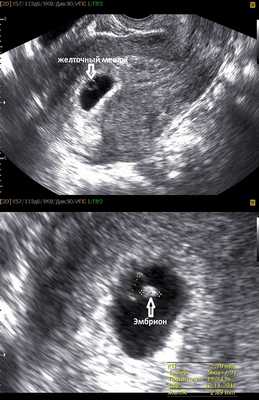

На этом сроке внутри плодного яйца появляется белое колечко - это желточный мешок.

В стенке желточного мешка образуются очаги эритропоэза, которые формируют капиллярную сеть, поставляя эритробласты (ядерные эритроциты) в первичную кровеносную систему плода. Желточный мешок является источником первичных половых клеток, которые мигрируют из его стенки к закладкам гонад эмбриона. До 6-й недели после оплодотворения желточный мешок, играя роль «первичной печени», продуцирует многие важные для эмбриона белки — альфа-фетопротеин, трансферрины, альфа2-микроглобулин. К концу I триместра беременности этот провизорный орган перестает функционировать и редуцируется.

Нормальные размеры желточного мешка 2-6 мм. Если в плодном яйце визуализируются два желточных мешка, значит это монохориальная многоплодная беременность. Но если внутри плодного яйца виден один желточный мешок, а эмбрион ещё отчётливо не визуализируется, то это всё ещё может оказаться монохориальная моноамниотическая двойня.

Эмбрион в начале 5-й недели практически неразличим на стенке желточного мешка, но уже к концу недели копчико-теменной размер (КТР) эмбриона достигает 3 мм.

СВД плодного яйца 11-16 мм.

Фото УЗИ плода при беременности 6-7 недель

Внутри плодного яйца мы видим "колечко с драгоценным камнем" :) - это желточный мешок и уже хорошо различимый эмбрион, расположенные рядом. Сердце эмбриона начинает биться в начале 6-й акушерской недели беременности. Именно наличие пульсации сердца является достоверным ультразвуковым признаком прогрессирующей беременности. При КТР ≥6 мм и отсутствии пульсации сердца делается заключение об остановке развития данного эмбриона. Нормальная частота сердечных сокращений (ЧСС) эмбриона в самом начале 6-й недели 70-90 ударов в минуту, но уже к концу недели становится более 100 уд. в мин. На ранних сроках беременности большее значение имеет не ЧСС, а как таковое наличие или отсутствие сердечных сокращений. Иногда, при неразвивающейся беременности можно увидеть отражение пульсации сосудов матери внутри эмбриона и принять их за сердцебиение ребёнка. Но в этом случае частота пульсации будет идентична ЧСС матери.

Наличие одного желточного мешка, одного эмбриона и одного пульсирующего сердца в подавляющем большинстве случаев говорит об одноплодной беременности. Но в очень редких случаях это могут в последствии оказаться неразделившиеся близнецы.

СВД плодного яйца 13-23 мм. КТР эмбриона 4-9 мм.